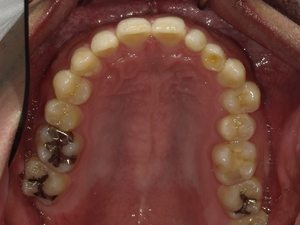

☆before→after☆◯ご相談内容:歯の叢生◯矯正の種類:マウスピース型矯正「インビザラインGO」◯治療期間:10週間◯治療費用:44万円(税込)